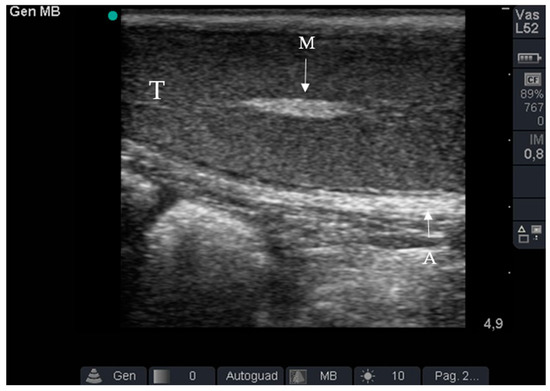

2.3. Ultrasound Examination

2.4. Surgical Approach

3. Results